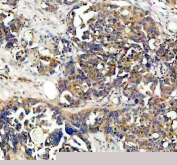

IHC staining of FFPE human ovarian cancer tissue with NQO1 antibody, HRP-secondary and DAB substrate. HIER: boil tissue sections in pH8 EDTA for 20 min and allow to cool before testing.